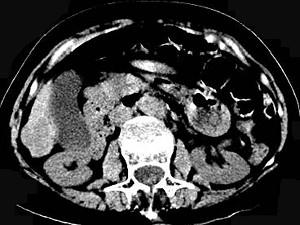

问题 女,70岁,发现乙型肝炎10年,3年前CT诊断为肝硬化,CT检查见图,最可能的诊断是 ( )

选项 A.肝癌 B.肝硬化、肝血管瘤 C.肝硬化、门脉瘤样扩张 D.肝门脉畸形 E.肝转移瘤、门脉扩张

答案 C